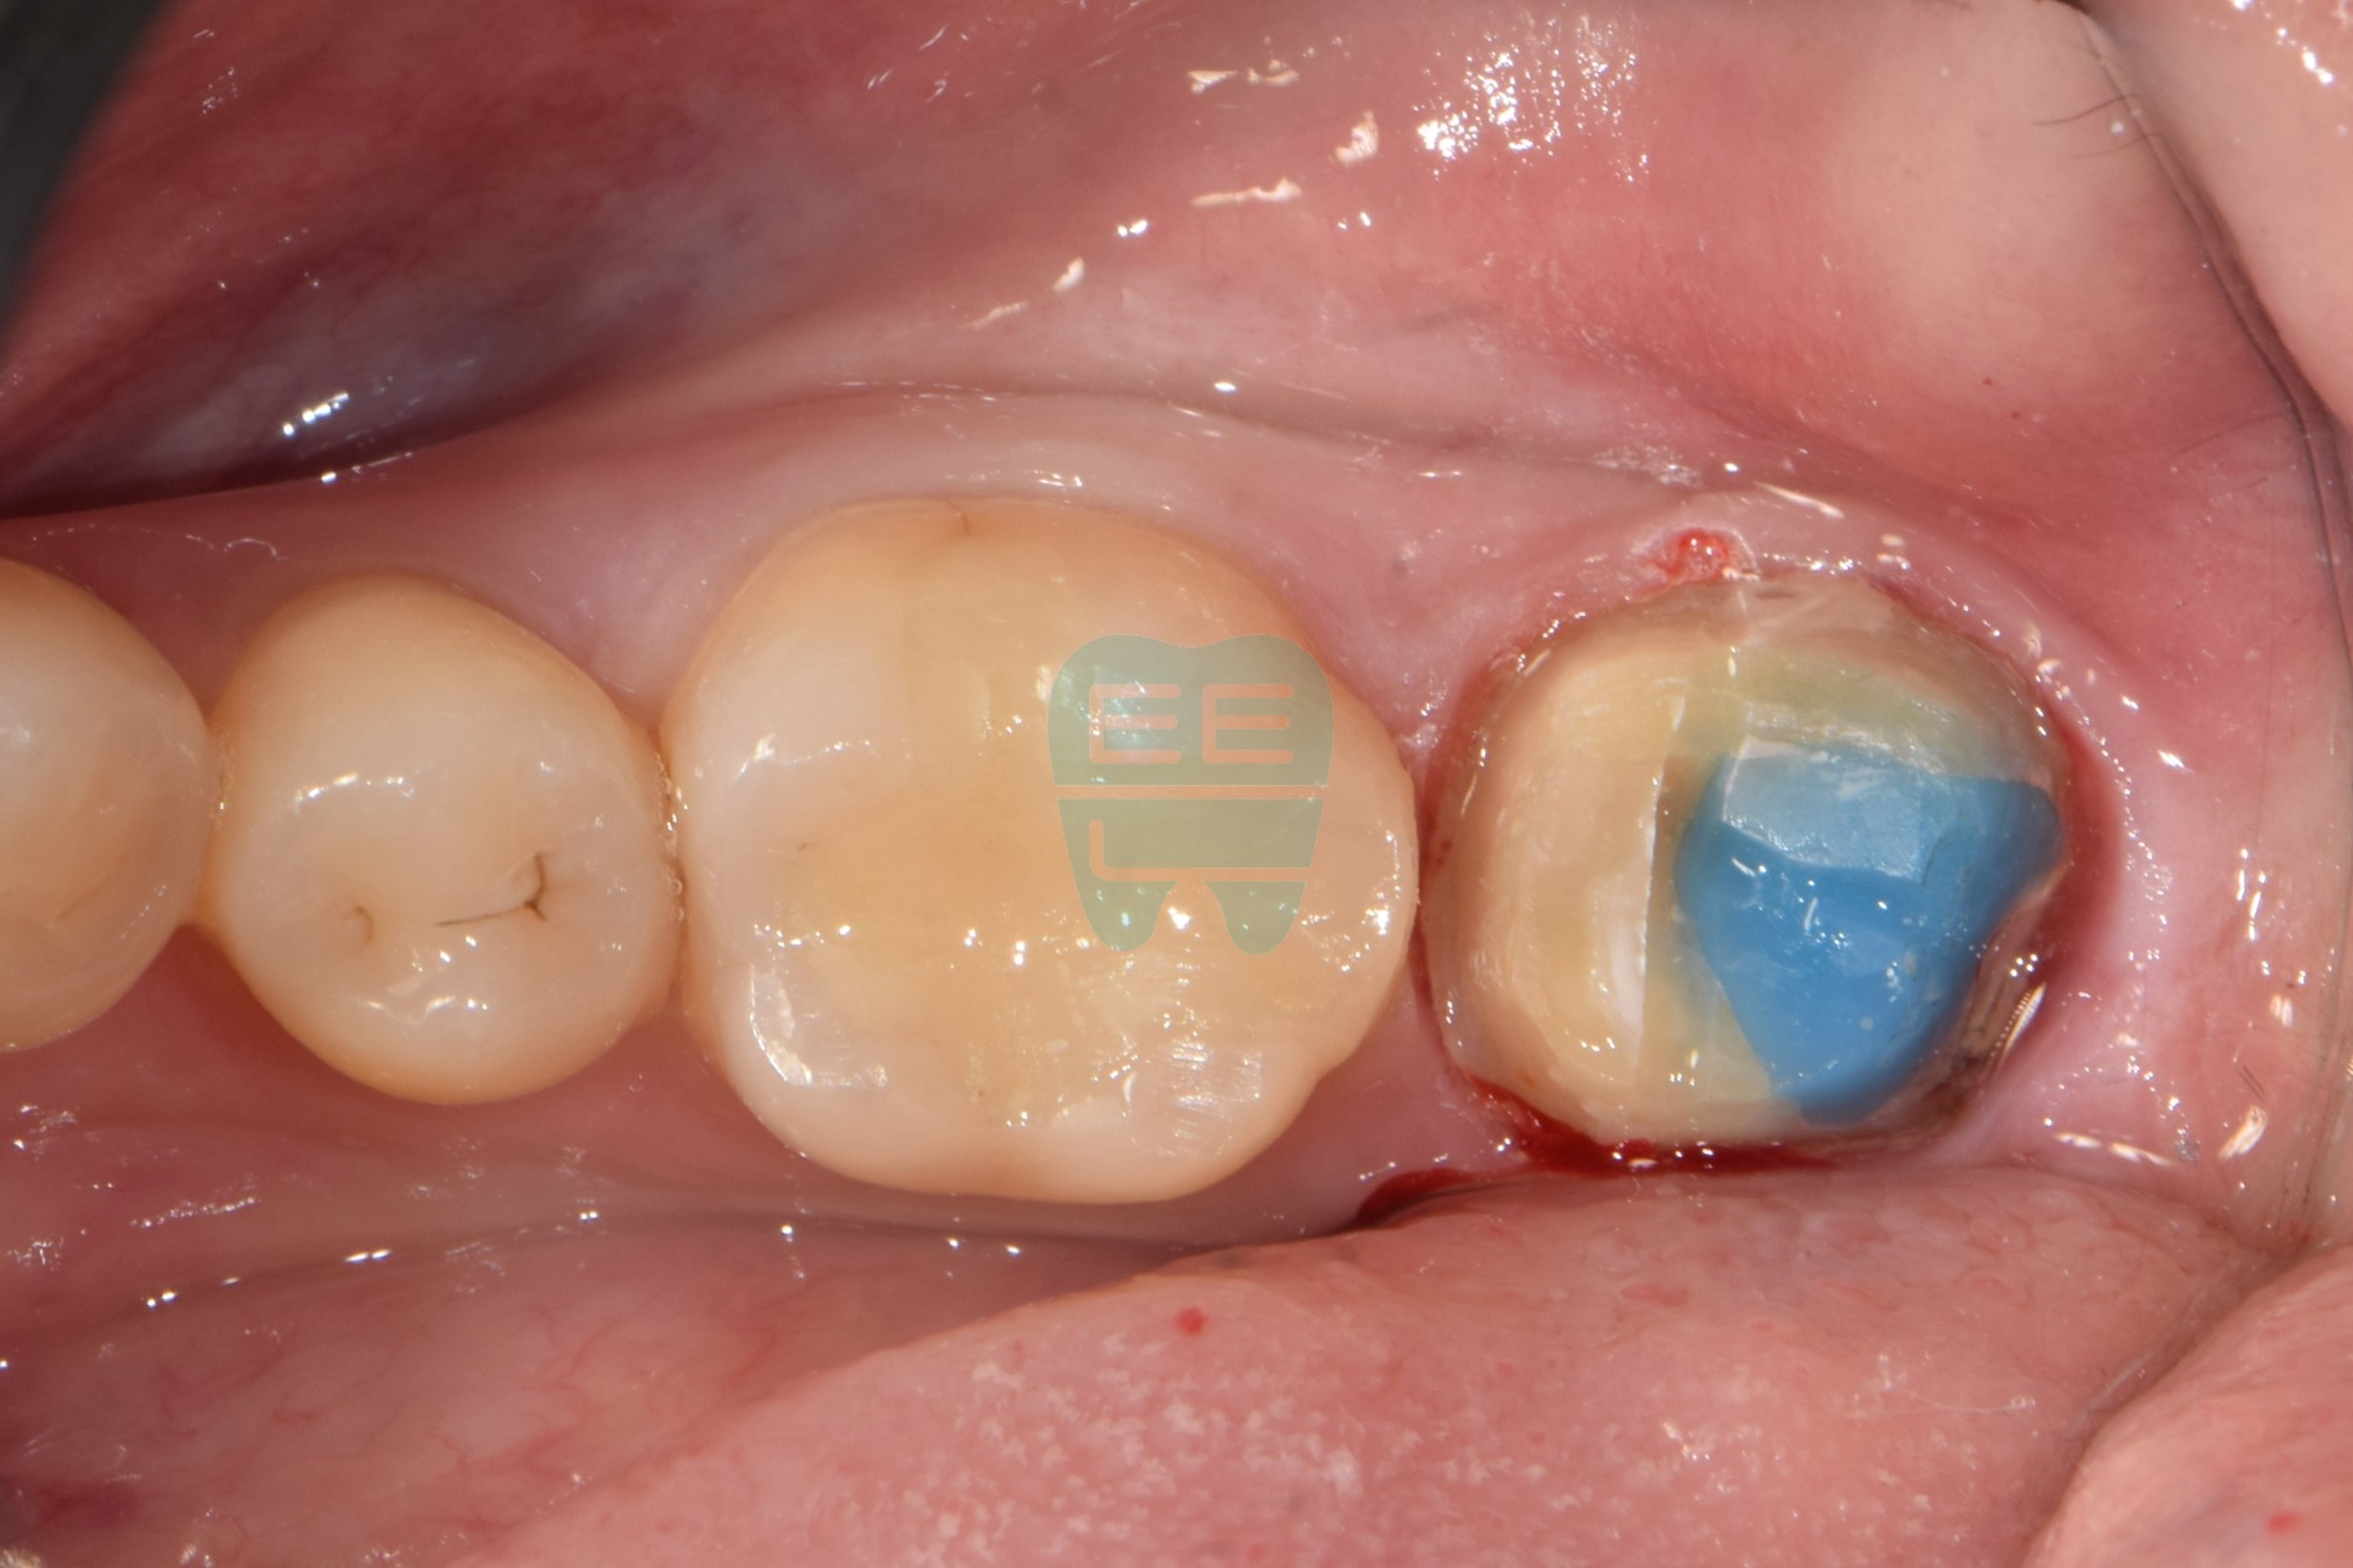

STEP 2. 지르코니아 크라운 제거 후 상태

크라운을 조심스럽게 제거하고 나니, 문제가 바로 눈에 들어왔습니다.

크라운 아래 원심(뒤쪽) 면을 따라 갈색으로 변색된 2차우식이 선명하게 보입니다. 기존 레진코어와 치아 사이의 경계 부위에서 leakage가 발생하여, 그 틈으로 세균이 침투한 것이 냄새의 원인이었습니다.